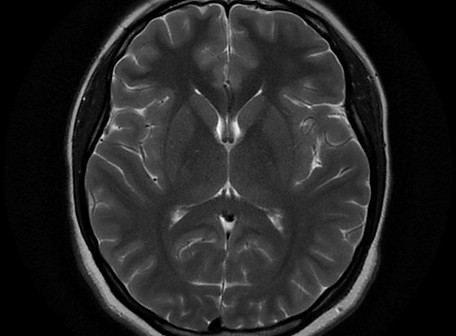

This the anatomical structure of brain. It will will explain about brain planes, brain lobes and cross-sectional of brain anatomy in MRI